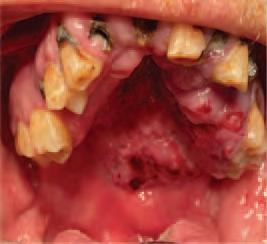

Issuu converts static files into: digital portfolios, online yearbooks, online catalogs, digital photo albums and more. Sign up and create your flipbook.